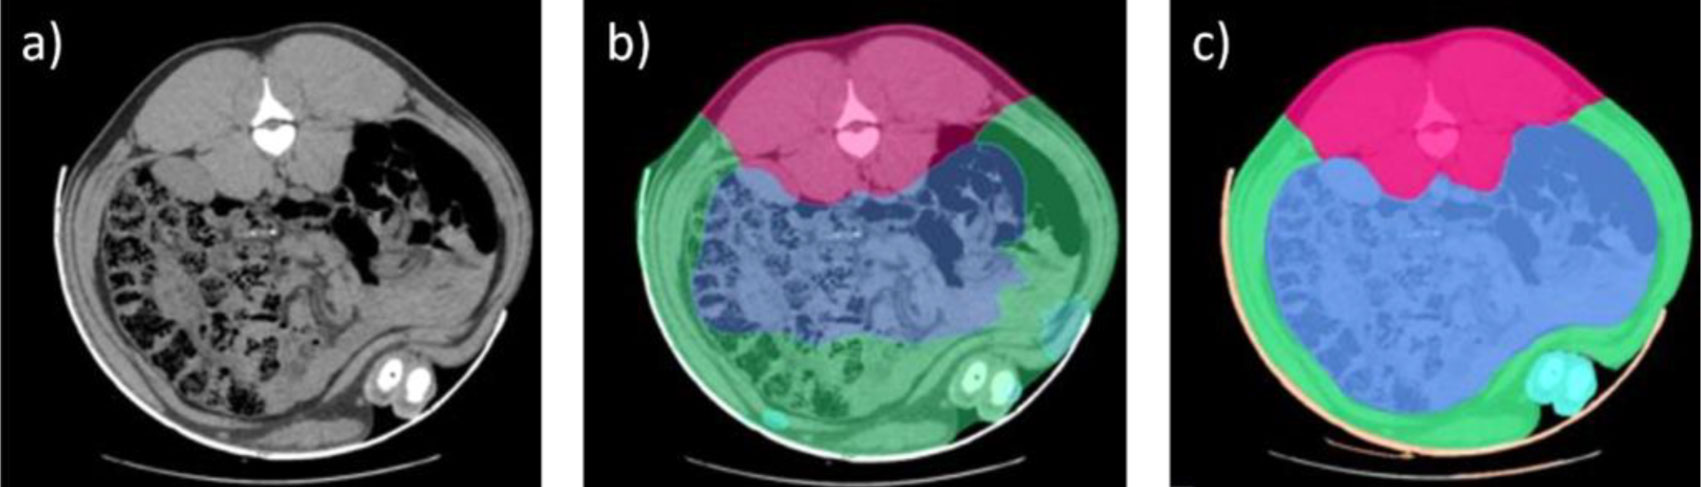

El proceso de análisis de las imágenes se realizó durante años de forma manual, identificando las diferentes áreas anatómicas y tipos de tejidos (hueso, grasa y músculo) lo que ya supuso un avance notable. En 2016, se implementó un primer método más automático de análisis de imágenes de TC que permitía discernir entre las diferentes piezas principales (jamón, paleta, lomo y panceta). La irrupción de las tecnologías de Inteligencia Artificial (IA) fue clave en la automatización de este proceso, fundamental para poder escalar esta herramienta y aumentar el número de animales analizados de forma más eficiente.

No obstante, la IA requiere de un proceso de entrenamiento previo para lo cual es necesaria una base de datos enorme con imágenes previamente analizadas que sirvan de modelo. En nuestro caso, esa base de datos estaba disponible gracias a los años previos de análisis con TC, durante los cuales ya se había avanzado notablemente en la segmentación de los tejidos e identificación en la imagen de los voxel (unidades más pequeñas que componen una imagen tridimensional, similar a los pixel en una fotografía) que pertenecen a tejidos diferentes.